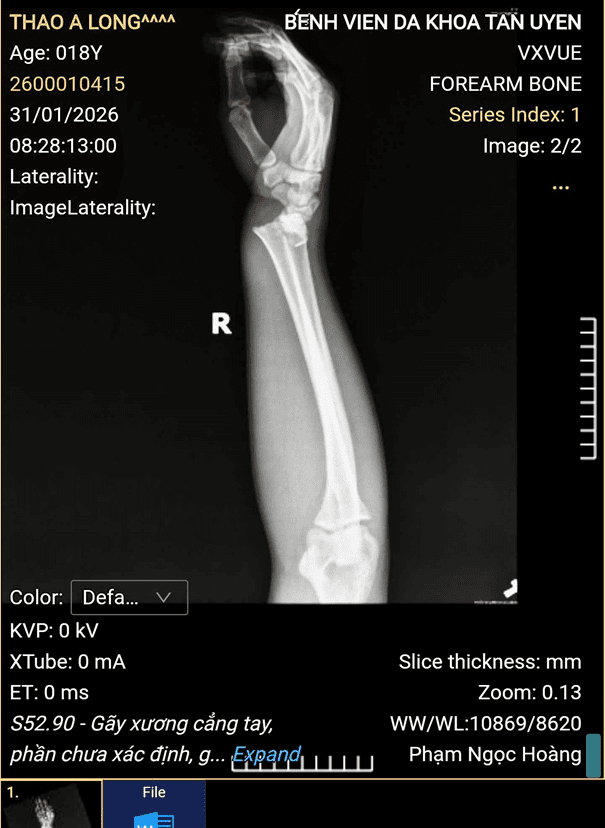

Khi vào viện, bệnh nhân trong tình trạng đau nhiều, hạn chế vận động cẳng tay hai bên, kèm theo xây xát da vùng mặt. Ngay sau khi tiếp nhận, bệnh nhân được các bác sĩ, điều dưỡng Khoa Ngoại phối hợp với các khoa liên quan khẩn trương thăm khám, chụp X-quang và làm các xét nghiệm cần thiết. Kết quả chẩn đoán xác định bệnh nhân bị gãy đầu dưới xương quay hai bên.

Hình ảnh của bệnh nhân và Bác sĩ Khoa Ngoại:

Hình ảnh của bệnh nhân trước khi kéo nắn.